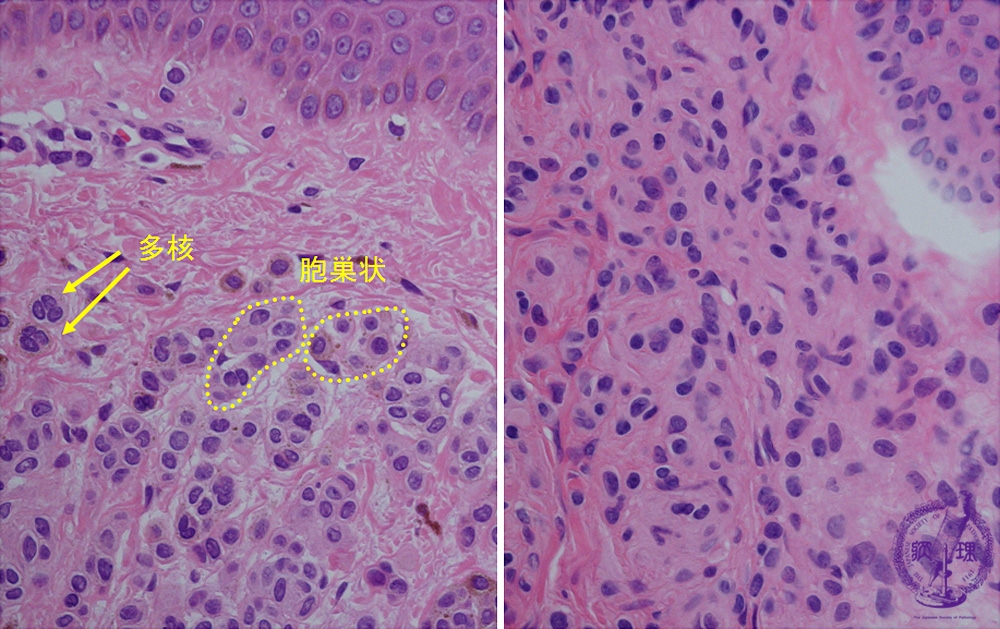

- (5)Melanocytic nevus (intradermal, junctional, compound)

Nevus cells form nests at the superficial dermis. Sometimes multinuclear nevus cells also exist (left). At the deep dermis, smaller nevus cells scatter. Cytoplasmic border of the nevus cells are obscure.